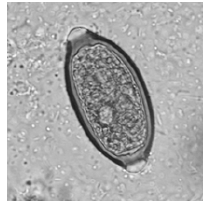

Durante um exame parasitológico de fezes você avistou a seguinte estrutura:

Fonte: Atlas de parasitologia clínica - www. parasitologiaclinica.ufsc.br

Ao reportar o laudo, você deve afirmar a presença de ovos de qual parasita?

Trichuris trichiura.